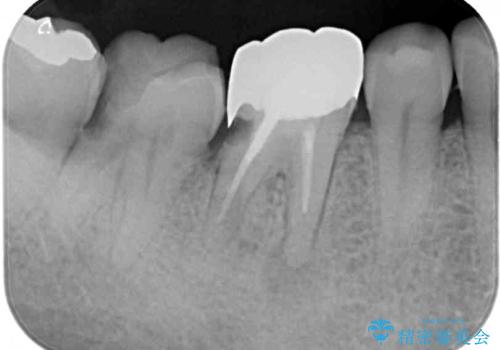

親知らずは速やかに抜歯し、手前の歯とその前の歯に歯槽骨にまで及んだ虫歯が認められたため、歯槽骨を削るなどの歯周外科処置を行うこととしました。

外科処置後の経過を待って、フルジルコニアクラウンにて補綴することとしました。